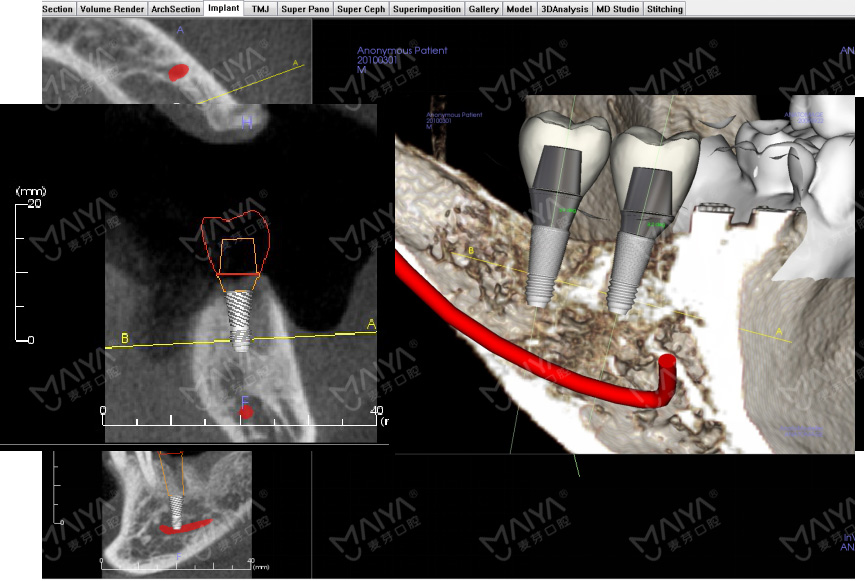

对于缺牙较多、多年缺牙未修复或牙槽骨吸收严重的人来讲,传统"盲种"一旦医生判断失误,就会导致种植体植入位置、角度不精确,造成日后种植牙受力不均、松动等情况,甚至直接导致种植失败。为规避"盲种"风险,"麦芽MAC数字化精确种植牙"应用口腔领域的数字化技术,通过CBCT、AI口扫取模、AI智能口腔体检等精确获取患者全口牙床位置,牙槽骨深度、厚度及角度等信息,并能直接在计算机上建成3D模型,全面向医生提供患者精确的颌面部影像数据。好比一幅带有导航仪的地图,医生能根据每名患者的口腔情况,精确制定个性化治疗方案,精确定位种植体理想位置。

此外,"麦芽MAC数字化精确种植牙"中的数字化分析模拟与方案设计、手术模拟导航技术等,能在计算机软件中预先设计种植方案,再通过3D可视化技术和3D打印技术制作种植导板,由此精确避开神经、血管位置,让种植牙牢牢地扎下根,彻底告别了传统"盲种"切开、翻开牙肉、缝合、拆线等步骤的弊端,同时大大缩短手术时间,患者身体负担更少,术后恢复更快。值得一提的是,MAC数字化精确种植牙还能对患者的牙颌面影像进行二次分析和处理,在计算机上精确呈现方案设计界面,模拟种植,让患者全程参与其中,并提前预知自己的种牙效果。